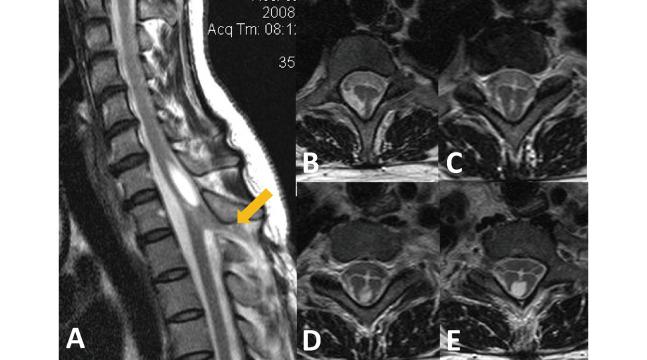

Dermal sinus tracts (DSTs) of the cervical and thoracic spine are extremely rare, particularly in adult patients because diagnosis is typically made in the early stage after birth by pediatricians. These cases should be treated surgically as soon as possible to prevent neurological sequelae. This report describes two rare adult cases with cervical and thoracic spine DSTs. The first patient presented with back pain and headache, whose skin lesion had been long known, but disregarded since birth. The second patient had long suffered from residual cervical myelopathy from the prior incomplete surgical treatment. Both cases had these sinus tracts excised completely and had spinal cord untethered successfully without any neurological deterioration. There has been a trend toward earlier diagnosis of these entities, but still some cases that were diagnosed in a delayed fashion or underwent incomplete treatment are reported. Improper management during childhood could lead to irreversible neurological deficit caused by spinal cord tethering and/or direct compression due to DSTs-associated tumors. The early detection and prompt surgical intervention improve the chance of a good surgical outcome. Furthermore, complete excision of the sinus tracts and associated tumors could help prevent future bacterial contamination and recurrence.

颈椎和胸椎的皮样窦道(DSTs)极为罕见,在成年患者中尤其如此,因为通常由儿科医生在出生后早期做出诊断。这些病例应尽快接受手术治疗,以预防神经后遗症。本报告描述了两例罕见的成年颈椎和胸椎DSTs病例。首例患者表现为背痛和头痛,其皮肤病变自出生以来就一直存在,但一直被忽视。第二例患者长期患有先前不完全手术治疗遗留的颈髓病。两例均将这些窦道完全切除,并成功解除脊髓栓系,未出现任何神经功能恶化。目前对于这些病变有早期诊断的趋势,但仍有一些病例报告诊断延迟或治疗不彻底。儿童期管理不当可能导致因脊髓栓系和/或DSTs相关肿瘤直接压迫而造成不可逆转的神经功能缺损。早期发现并及时进行手术干预可提高获得良好手术效果的机会。此外,彻底切除窦道及相关肿瘤有助于预防未来的细菌污染和复发。